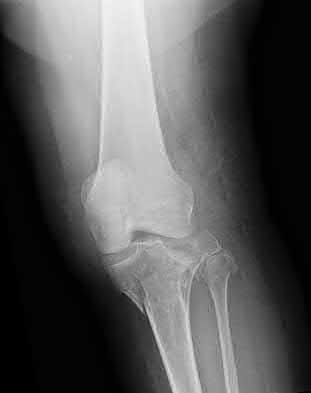

1. # A 32-year-old male sustains the injury shown in Figure A and undergoes treatment as shown in Figure B. Following placement of this implant, what is the best technique to confirm it is not too proud proximally?

1. Lateral radiograph of the knee

2. AP radiograph of the knee

3. Oblique radiographs of the knee

4. Merchant radiograph of the knee

5. Internally rotated 45 degree view of the knee Corrent answer: 1

The safe zone for tibial nail placement as seen on radiographs is just medial to the lateral tibial spine on the anteroposterior radiograph and immediately adjacent and anterior to the articular surface as visualized on the lateral radiograph.

Tornetta et al specifically located the safe zone for nail entry in a study using fresh frozen cadaver knees. The authors found that the safe zone for nail placement is located 9.1+/-5 millimeters lateral to the midline of the plateau and three millimeters lateral to the center of the tibial tubercle. The width of the safe zone averaged 22.9 millimeters and was as narrow as 12.6 millimeters.

The starting point of the of the nail can be best viewed on the lateral knee radiograph, an example of which is shown in Illustration A. Illustration B shows the "sweet spot" for nail insertion as defined by Tornetta.